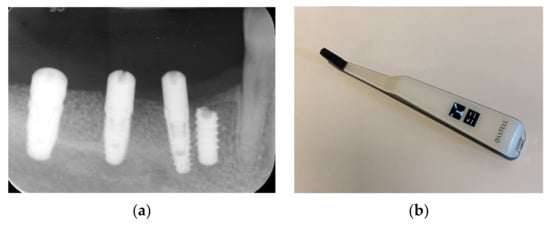

9. Prosthetic Treatment

After 3 months of osseointegration, healing abutments were placed, and the implant stability was evaluated with a resonance frequency analysis (RFA) and ISQ values utilizing the Osstell device, showing great implant stability (Table 1) (Figure 18a–d).

Table 1.

Insertion torque and ISQ values.

Figure 18.

Stability ISQ measurements (a–d).